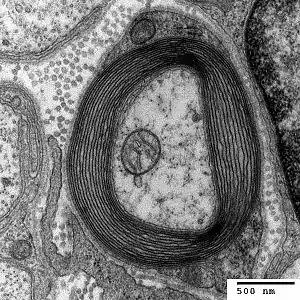

The peripheral blood and bone marrow aspirate findings in copper deficiency can mimic myelodysplastic syndrome.[8] Bone marrow aspirate in both conditions may show dysplasia of blood cell precursors and the presence of ring sideroblasts (erythroblasts containing multiple iron granules around the nucleus). Unlike most cases of myelodysplastic syndrome, the bone marrow aspirate in copper deficiency characteristically shows cytoplasmic vacuoles within red and white cell precursors, and karyotyping in cases of copper deficiency does not reveal cytogenetic features characteristic of myelodysplastic syndrome.[6][7]

Another hypothesis is that copper deficiency myelopathy is caused by disruptions in the methylation cycle.[10] The methylation cycle causes a transfer of a methyl group (-CH3) from methyltetrahydrofolate to a range of macromolecules by the suspected copper dependent enzyme methionine synthase.[10] This cycle is able to produce purines, which are a component of DNA nucleotide bases, and also myelin proteins.[10] The spinal cord is surrounded by a layer of protective protein coating called myelin (see figure). When this methionine synthase enzyme is disrupted, the methylation decreases and myelination of the spinal cord is impaired. This cycle ultimately causes myelopathy.[10]

The anemia caused by copper deficiency is thought to be caused by impaired iron transport. Hephaestin is a copper containing ferroxidase enzyme located in the duodenal muscosa that oxidizes iron and facilitates its transfer across the basolateral membrane into circulation.[6] Another iron transporting enzyme is ceruloplasmin.[6] This enzyme is required to mobilize iron from the reticuloendothelial cell to plasma.[6] Ceruloplasmin also oxidizes iron from its ferrous state to the ferric form that is required for iron binding.[4] Impairment in these copper dependent enzymes that transport iron may cause the secondary iron deficiency anemia.[6] Another speculation for the cause of anemia is involving the mitochondrial enzyme cytochrome c oxidase (complex IV in the electron transport chain). Studies have shown that animal models with impaired cytochrome c oxidase failed to synthesize heme from ferric iron at the normal rate.[6] The lower rate of the enzyme might also cause the excess iron to clump, giving the heme an unusual pattern.[6] This unusual pattern is also known as ringed sideroblastic anemia cells.